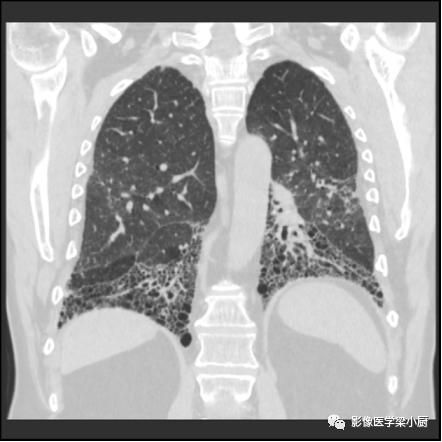

3.蜂窝:呈镞状囊性低密度影,囊壁光整,厚度1~3mm,直径常为3~10mm,偶尔可达2.5cm。蜂窝是HRCT的UIP型最具特征性的表现,蜂窝影预测UIP的灵敏度和特异度较高。

蜂窝的组成目前尚不清楚,推测为扩张的小气道,是纤维化进展的标志,提示预后差。

双肺呈弥漫蜂窝状改变